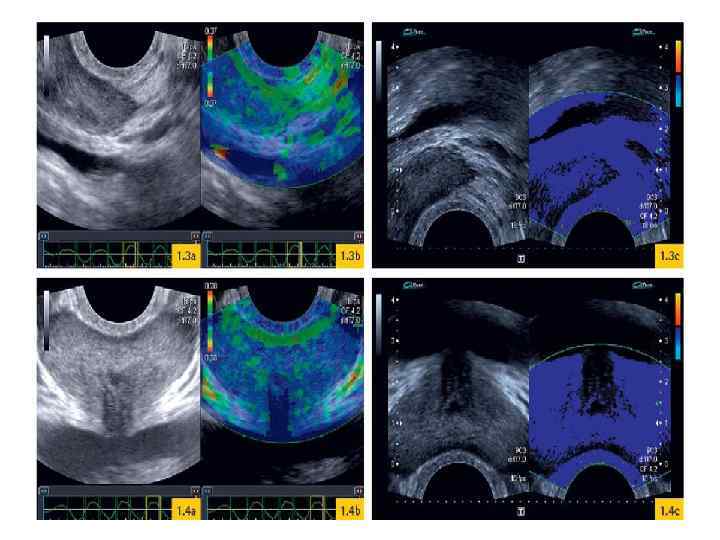

Эластография Метод основан на том, что ткань злокачественной опухоли является значительно более плотной, чем нормальная. С помощью эластографии производится измерение эластических свойств тканей железы во время компрессии датчиком и их представление на экране в виде зон различной цветовой окраски – это качественная оценка. Так же у некоторых фирм-производителей ультразвуковой аппаратуры имеются аппараты с количественной оценкой эластичности опухолевой ткани в процентном отношении к здоровой.